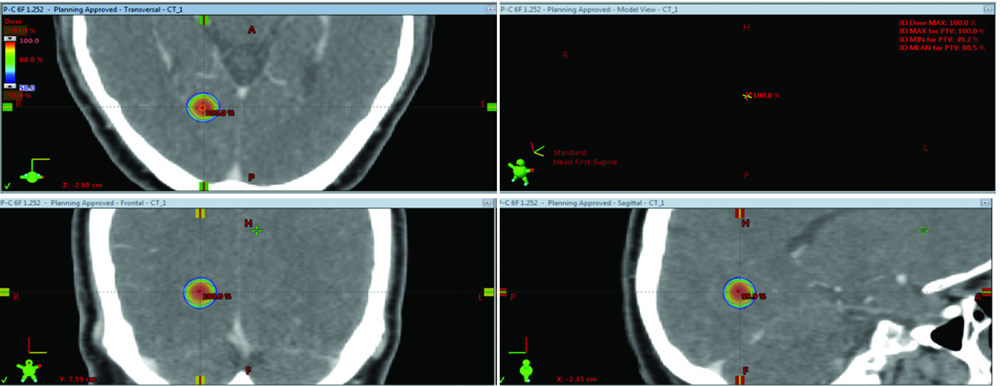

| [2] | 赵永瑞, 高莹, 陈怡东, 徐建堃.基于直线加速器的分次立体定向放疗对小体积脑转移瘤的有效性及安全性[J]. 国际肿瘤学杂志, 2023, 50(3): 138-143. |